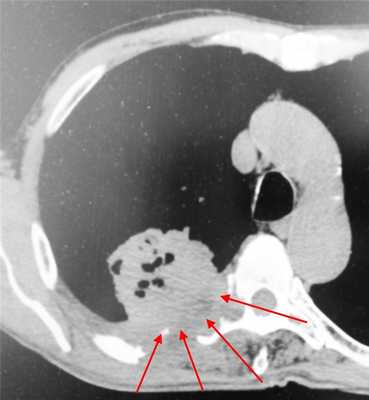

Пример рака легких 4 стадии. Не показано оперативное лечение, только химиотерапия. Имеет место прорастание в ребра и позвоночник, а также в мягкие ткани грудной стенки. В строме опухоли видны множественные гиподенсные (темные) участки, содержащие газ - зоны распада.